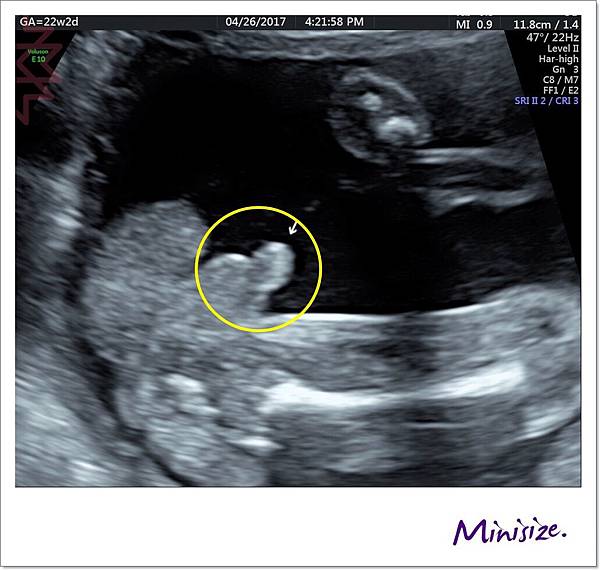

眼

是我覺得最有趣的超音波照片

寶寶長得好像外星人的臉蛋

哈哈哈

這邊檢查兩個眼眶

眼框裡箭頭處兩個白白的點就是眼睛喔